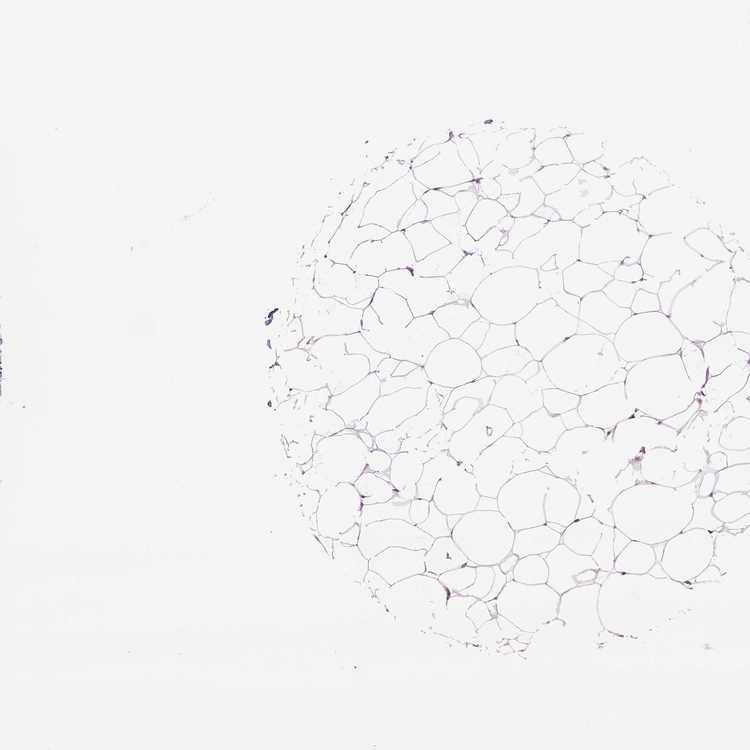

BREAST - Antibody stainingi

Antibody staining in the annotated cell types in the current human tissue is reported as not detected, low, medium, or high, based on conventional immunohistochemistry profiling in selected tissues. This score is based on the combination of the staining intensity and fraction of stained cells.

Each image is clickable and will lead to virtual microscopy that enables deeper exploration of all samples and also displays staining intensity scores, fraction scores and subcellular localization as well as patient and tissue information for each sample.

Antibody HPA073761

Adipocytes Not detected

Glandular cells Not detected

Myoepithelial cells Not detected